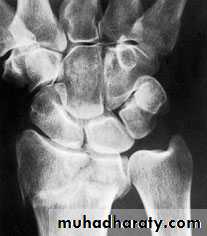

X-RAY

There is a transverse fracture of the radius at the corticocancellous junction, and often the ulnar styloid process is broken off. The radial fragment is impacted into radial and backward tilt. Sometimes there is an intra-articular fracture; sometimes it is severely comminuted.TREATMENT